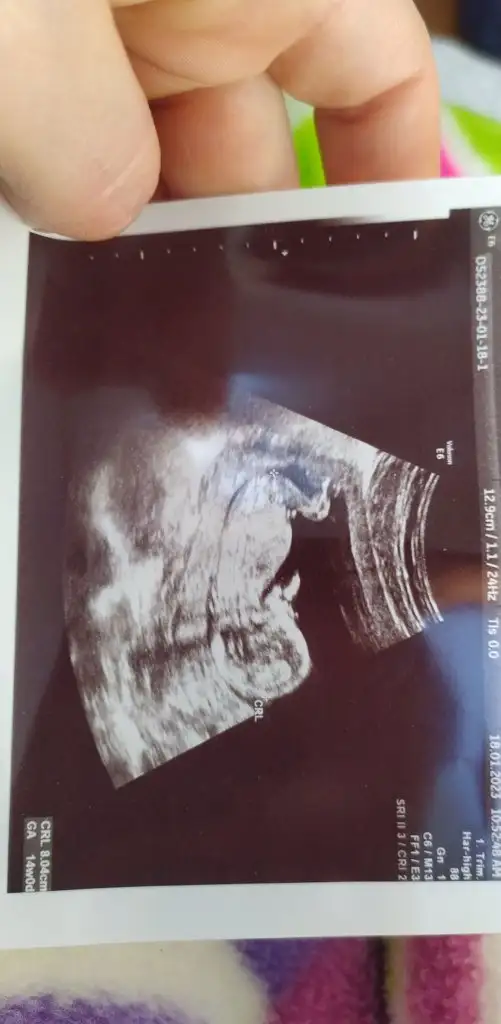

Bu 12 haftalık görüntüsü burda belli olmadı da 15 sinci haftadami belli oldu kafamı bu karıştırıyor

Evet bunda çok belli değil aslında ve hangi haftada göründüğü önemli değil görünmüş olması yeter ve bende kağıda tekrar baktım sen erken yatırmışsın tam 12+0 olmadan yapılmıyor doktorun hatası inşallah sağlıkla gelecek bebeğin ve bunların hepsi geçecek gazıyla uykusuyla uğraşacaksın 🤲🤲

Elini zaten burnunun üstüne koymuş nasıl gördük kemik olmadığını resmen eli üstünde anneler böle bizden çok panik oluyorlar haklılarda işte genede panik yapmadan başka doktora damı gitsen ki